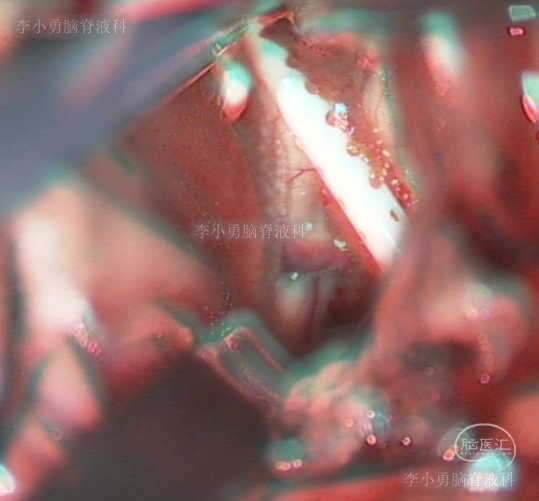

当天进行了开颅手术,术中发现脑室内引流管再次被脉络丛粘连,并切除脉络丛(图-21)。

图-21:术中过程